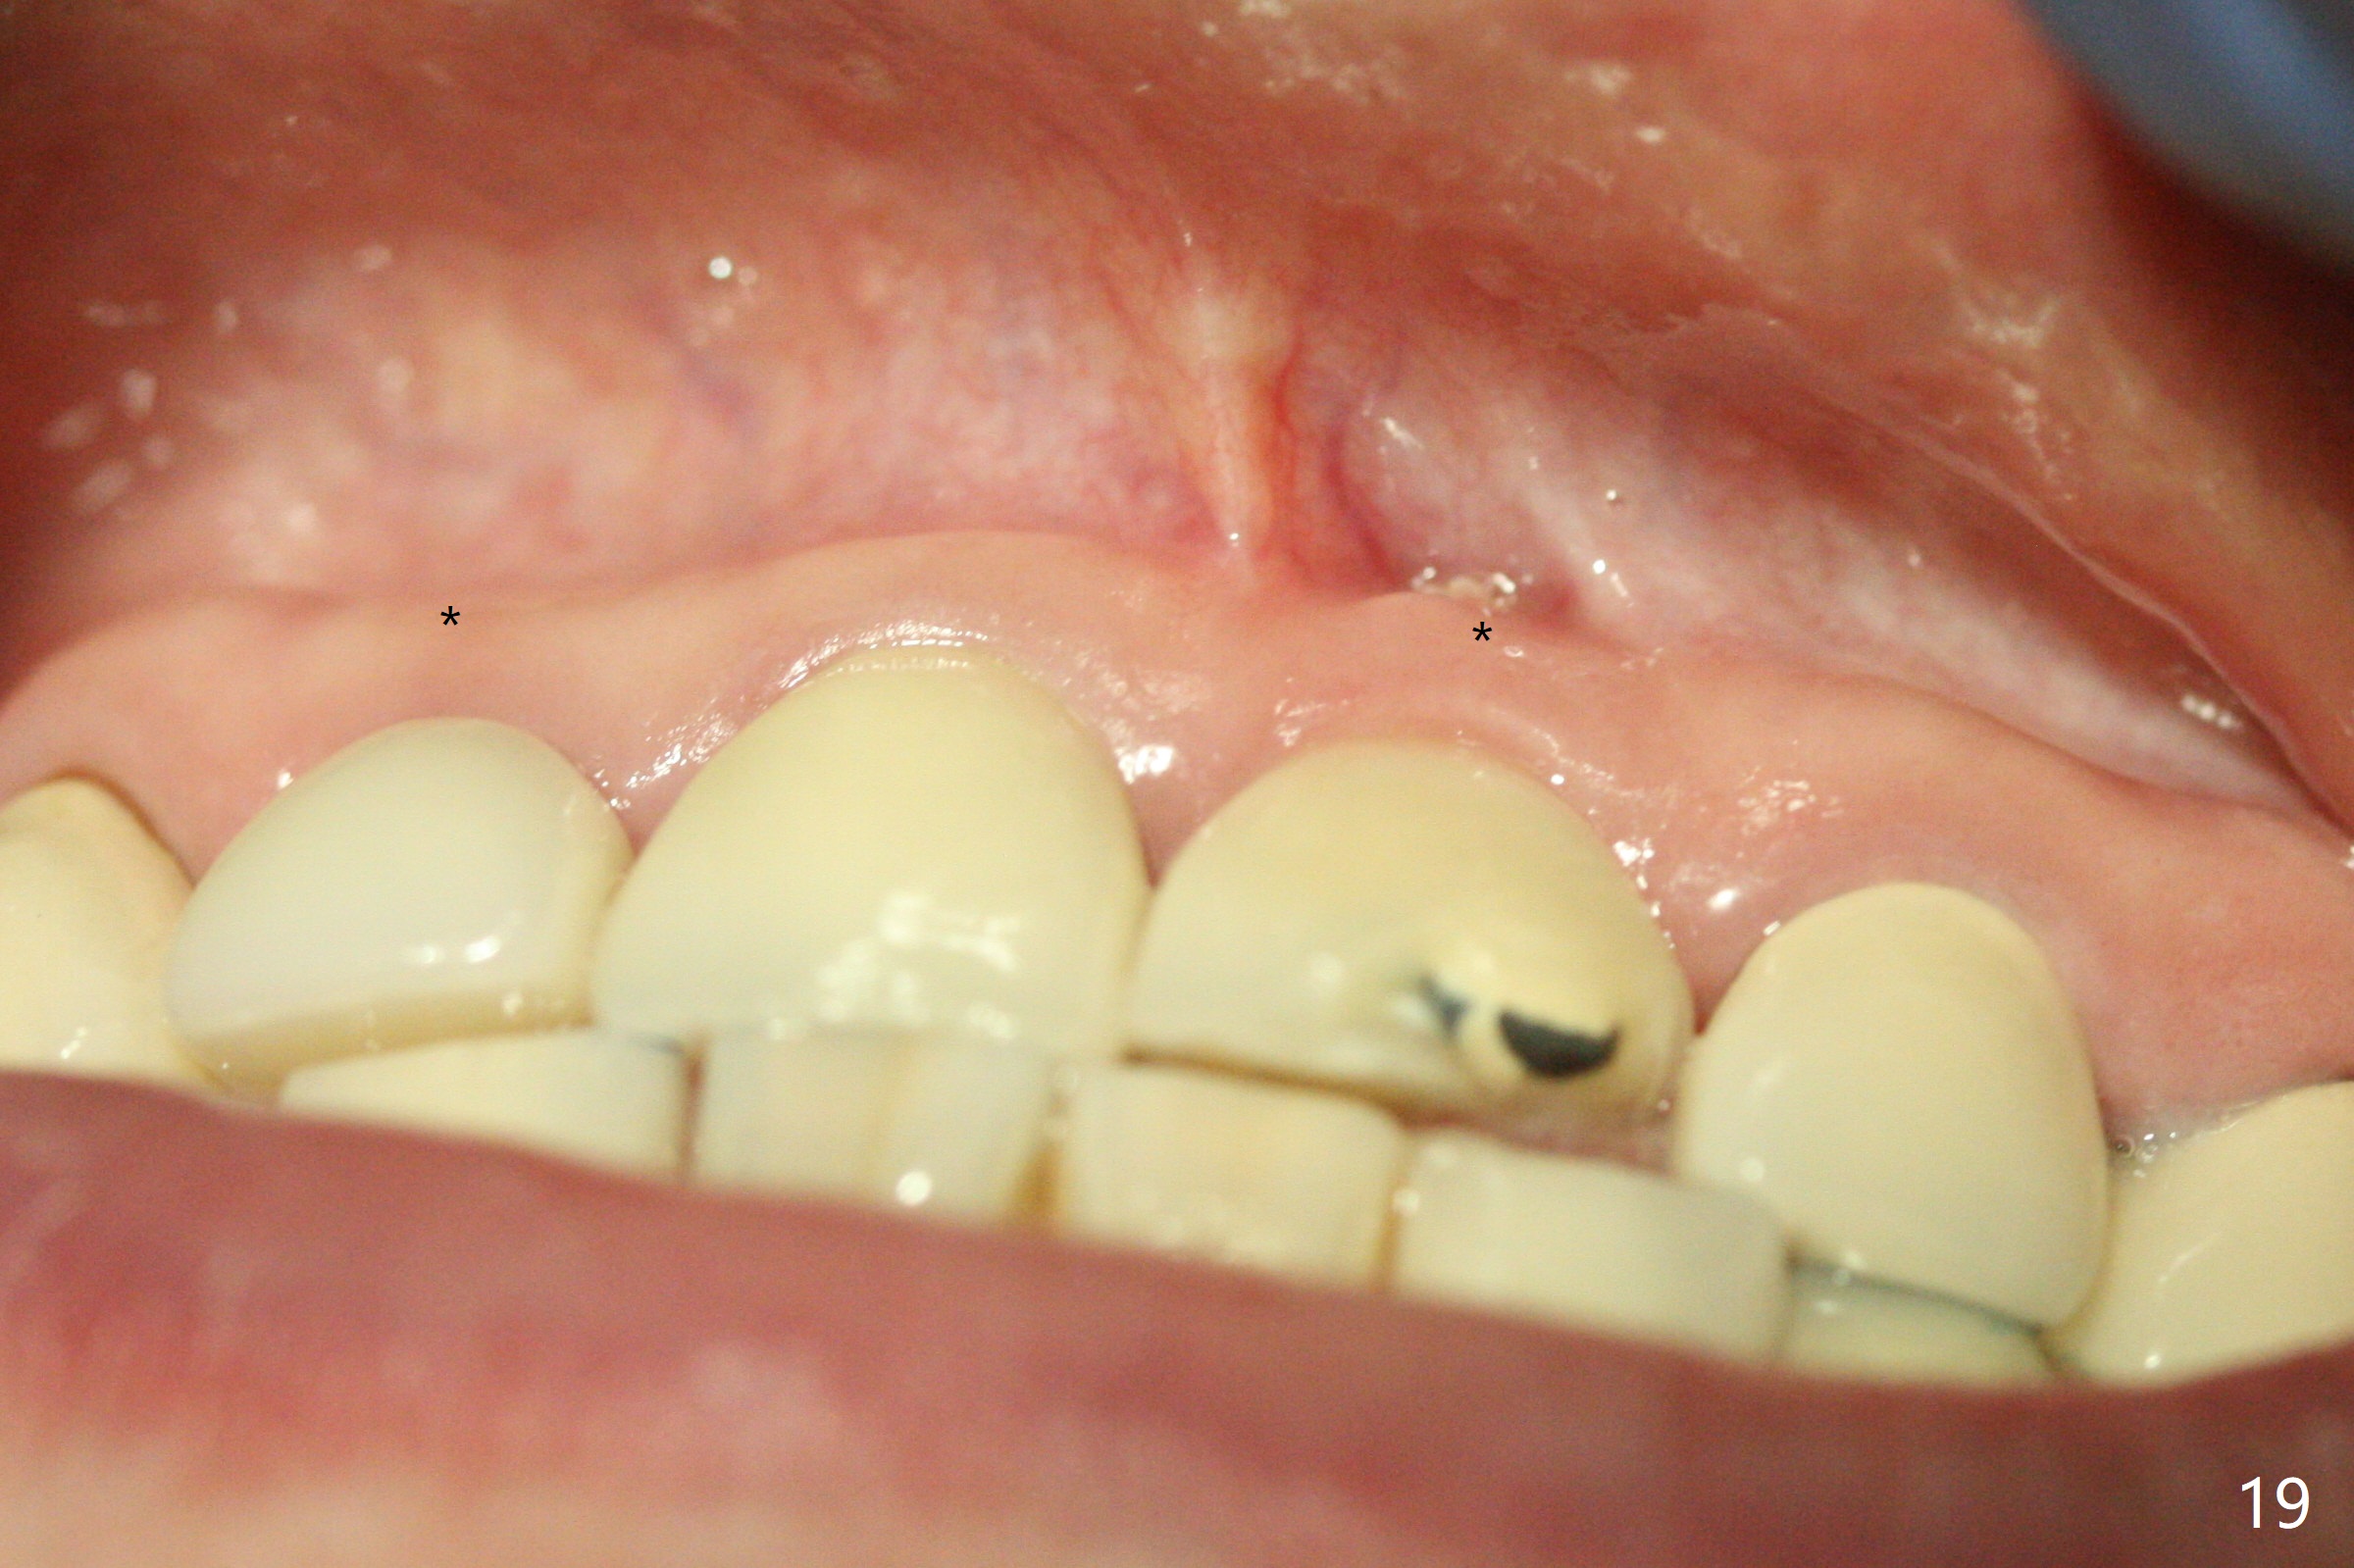

The buccal contour at #9 seems to be slightly concave preop (Fig.1,2 (*)). In fact the buccal plate is found to be lost when the tooth is extracted. Osteotomy is initiated as palatal as possible apical, but the occlusion dictates the coronal end of the osteotomy should be buccal, leaving the buccal gap ~ 2 mm for bone graft. The initial osteotomy (18 mm deep) appears to be close to the Incisive Foramen (Fig.3 blue dashed line). The nasal floor appears to be intact when the drill is removed. Subsequent osteotomy is adjusted so that the apical end of the osteotomy moves distal; when a 3.8x15 mm dummy implant is partially placed, there is clearance (Fig.4). It remains so when a definitive implant is seated (Fig.5); Vanilla graft is placed (Fig.5 *) before placement of a 4.5x5.5(3) mm abutment. More allograft is placed when an immediate provisional is fabricated (Fig.6 arrow and *). The gingiva remains to be recessive 1 month postop (Fig.7). It seems to be related to the bulky gingival margin of the provisional (Fig.8 *). After trimming the latter (Fig.9 *), the gingival margin immediately returns close to normal (Fig.10). The gingival margin is even between #8 and 9 two months postop, but the bone graft is exposed apically (Fig.11 ^). It may heals by itself. Otherwise debridement, regraft, PRF and suture are pending. The coronal portion of the socket heals 4 months postop (Fig.12). The gingival cuff forms by the immediate provisional (which is removed for impression) 4 months postop (Fig.13 *). While the full Zirconia crown at #7 remains intact (Fig.14), the PFM at #9 has porcelain chip (Fig.15). It is partially due to the occlusion; while the crown at #7 has clearance with the opposing dentition (Fig.16 *), the one at #9 has no. The access hole at #9 (Fig.17 *) seems to weaken the crown structure. There is no access hole at #7. No solid posterior support is another contributing factor for chip (Fig.18). The buccal plate has mild atrophy at #7 and 9 (Fig.19 *). A piece of bone graft is being expelled apically at #9 (Fig.20 >) and is removed subsequently (Fig.21). Before impression for repacking porcelain, the opposing incisal edge has been shortened (Fig.22 arrows, as compared to Fig.16). Since the ideal access hole is at the incisal edge (Fig.25 black circle), buccal to the existing one (Fig.24 A), the abutment is torqued before the repaired crown is recemented (Fig.23). Finally the crown has occlusal clearance (Fig.26). Porcelain chips again around the access hole of PFM 1.5 years post 2nd cementation. The dense bone at the crest (*) cannot explain why the abutment is not loose, since it remains incompletely seated (>). As it was trimmed short, an angled abutment is used (Fig.28). The coronal end is lingual, while #9/24 is edge to edge. The lingual aspect of the coronal end of the abutment is heavily trimmed to reduce bulkiness. To prevent chip, Zirconium crown will be fabricated in spite of the fact that it does not match the PFM of #8 (potential shade discrepancy). The patient is pleased with the new Zirconia crown (Fig.29).